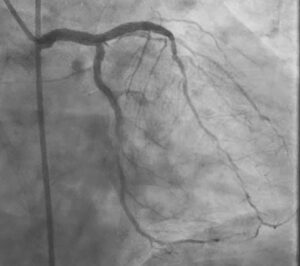

We recently managed a 76-year-old multimorbid patient who presented with NSTEMI, acute decompensated heart failure, and reduced left ventricular systolic function with an LVEF of 37%. Coronary angiography showed diffuse, heavily calcified triple-vessel disease, with poor surgical targets, and the patient was considered a surgical turndown.

Among the most challenging lesions was a heavily calcified chronic total occlusion (CTO) of the right coronary artery (RCA). This case highlights the importance of persistence, lesion preparation, intravascular imaging, and procedural support in achieving a successful result in complex calcific PCI.

The Real Challenge Began After Wiring the CTO

The RCA lesion was a heavily calcified CTO, and as expected, the procedure demanded more than simple wire passage.

The lesion was first wired with a Fielder XTA, successfully negotiating the occlusion. However, in complex calcified CTO PCI, crossing the wire is often only the beginning. The next major problem was that the lesion remained extremely resistant to device passage.

A microcatheter could not cross.

An attempt was then made with a Nicnano 0.85 balloon, but even this could not cross the lesion. This immediately confirmed the severity of calcium burden and the rigid nature of the plaque architecture.

At that point, it became clear that this was not a lesion that would yield to conventional balloon-based escalation alone. The strategy had to shift toward plaque modification.